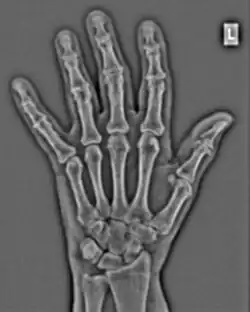

FFTs can also be calculated in two-dimensions to give results such as those in Figure 1.27. Since Fourier analysis generates results in terms of both positive and negative spatial frequencies, these can be plotted in the form of a 2D image so that the maximum frequency lies at the origin and those for the horizontal and vertical directions are shown increasing towards that origin. The modulation at different spatial frequencies is represented using a grey-scale. Low frequency bands can be seen along the horizontal axis in the figure, for example, representing the horizontal periodicity of image data from the fingers, while finer bands along the y-dimension are indicative of a periodicity of image data from the various metacarpophalangeal joints. Higher frequency features can also be seen running diagonally in this 2D-FFT, representative of the trabecular structure of the bones, for example.

The essence of this approach is that it can be used to produce a range of image processing effects by enhancing and/or suppressing features in the 2D-FFT and then converting the result back into the spatial domain using the IFT, as illustrated in Figure 1.28. Such image manipulations are considered in more detail in a later chapter. Note that the form of image processing demonstrated in the figure is for purely illustrative purposes and bears no direct medical significance.